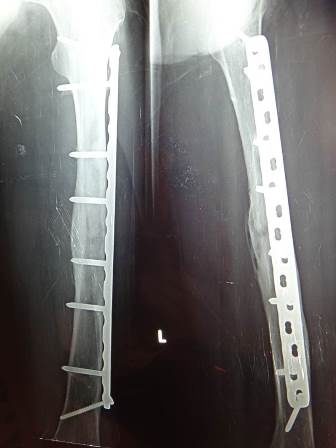

4 months later

5-year follow-up X-ray